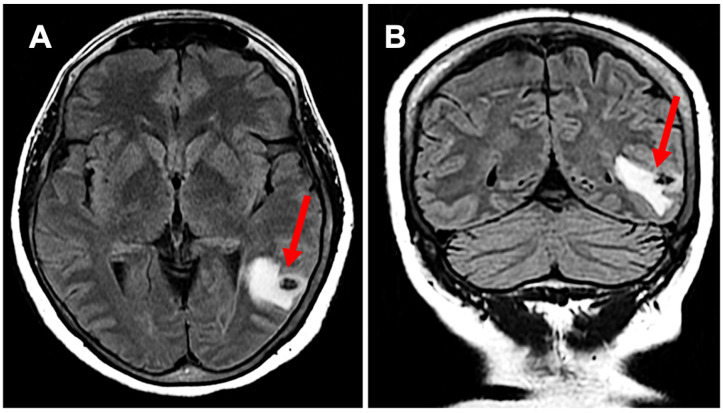

Neurocysticercosis (NCC), a parasitic infection caused by Taenia solium larvae, remains a leading cause of acquired epilepsy worldwide, particularly in regions with inadequate sanitation and healthcare access. We present a case of NCC reactivation in a 64-year-old female who developed anomic aphasia-a rare manifestation of NCC-decades after her initial diagnosis. The patient's clinical course was complicated by a potential trigger of semaglutide, which potentially attenuated the protective inflammatory response maintained by astrocytes and microglia, leading to the reactivation of dormant cysts. Brain imaging confirmed localized cystic changes, and treatment with antiparasitic agents and corticosteroids led to marked clinical improvement. This case highlights the complexity of NCC reactivation, highlighting the interplay of metabolic, immune, and parasitic factors. It emphasizes the need for vigilance in managing patients with dormant infections and investigating potential risks associated with novel therapeutic agents like GLP-1 receptor agonists. Further research is essential to unravel the mechanisms linking metabolic modulation to parasitic reactivation, offering insights into prevention and treatment strategies.

Abstract Image